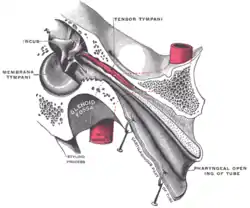

Horizontal section through left ear; upper half of section The right membrana tympani with the hammer and the chorda tympani, viewed from within, from behind, and from above

The right membrana tympani with the hammer and the chorda tympani, viewed from within, from behind, and from above Auditory tube, laid open by a cut in its long axis